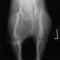

■ 症例24 キャバリア 7か月

左右膝蓋骨内方脱臼(左:グレードⅣ 右:グレードⅢ)

以前から左右後肢の跛行が認められ、整形外科学的検査・レントゲン検査により左右の膝蓋骨脱臼が認められた。症状が重度である左膝の膝蓋骨脱臼整復術を行った。外科手技は縫工筋及び内側広筋の解放、脛骨粗面の外側転位、滑車ブロック形造溝術、内外側関節方の縫縮を実施した。術後一か月時点で、左の膝蓋骨は安定しており経過は良好である。

本症例は成長期における重度の膝蓋骨脱臼であり、術後の再発の可能性もあるため、経過をしっかりと観察していく必要がある。また、今回手術を実施していない右膝に関しても経過を観察し、手術を検討していくこととする。